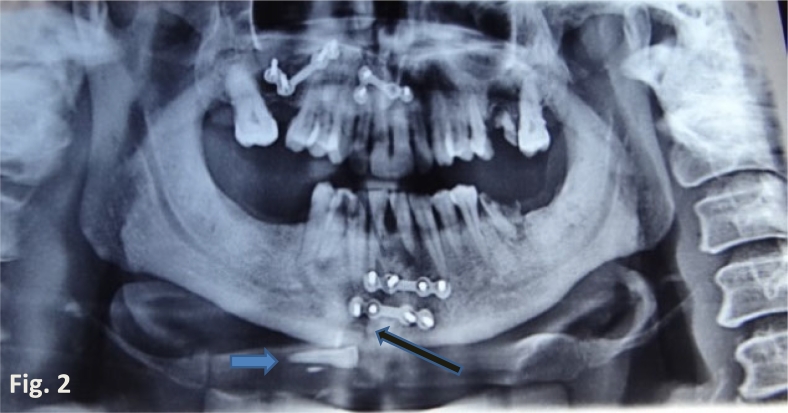

The dental clinicians noticed the swelling to his submental space and conducted a panoramic radiograph to evaluate the fracture site. The radiograph clearly showed a displaced central incisor lying at the base of the parasymphysis near the fracture site. The dental surgeon operated the region, removing the unusually displaced tooth from the man’s chin via surgery.